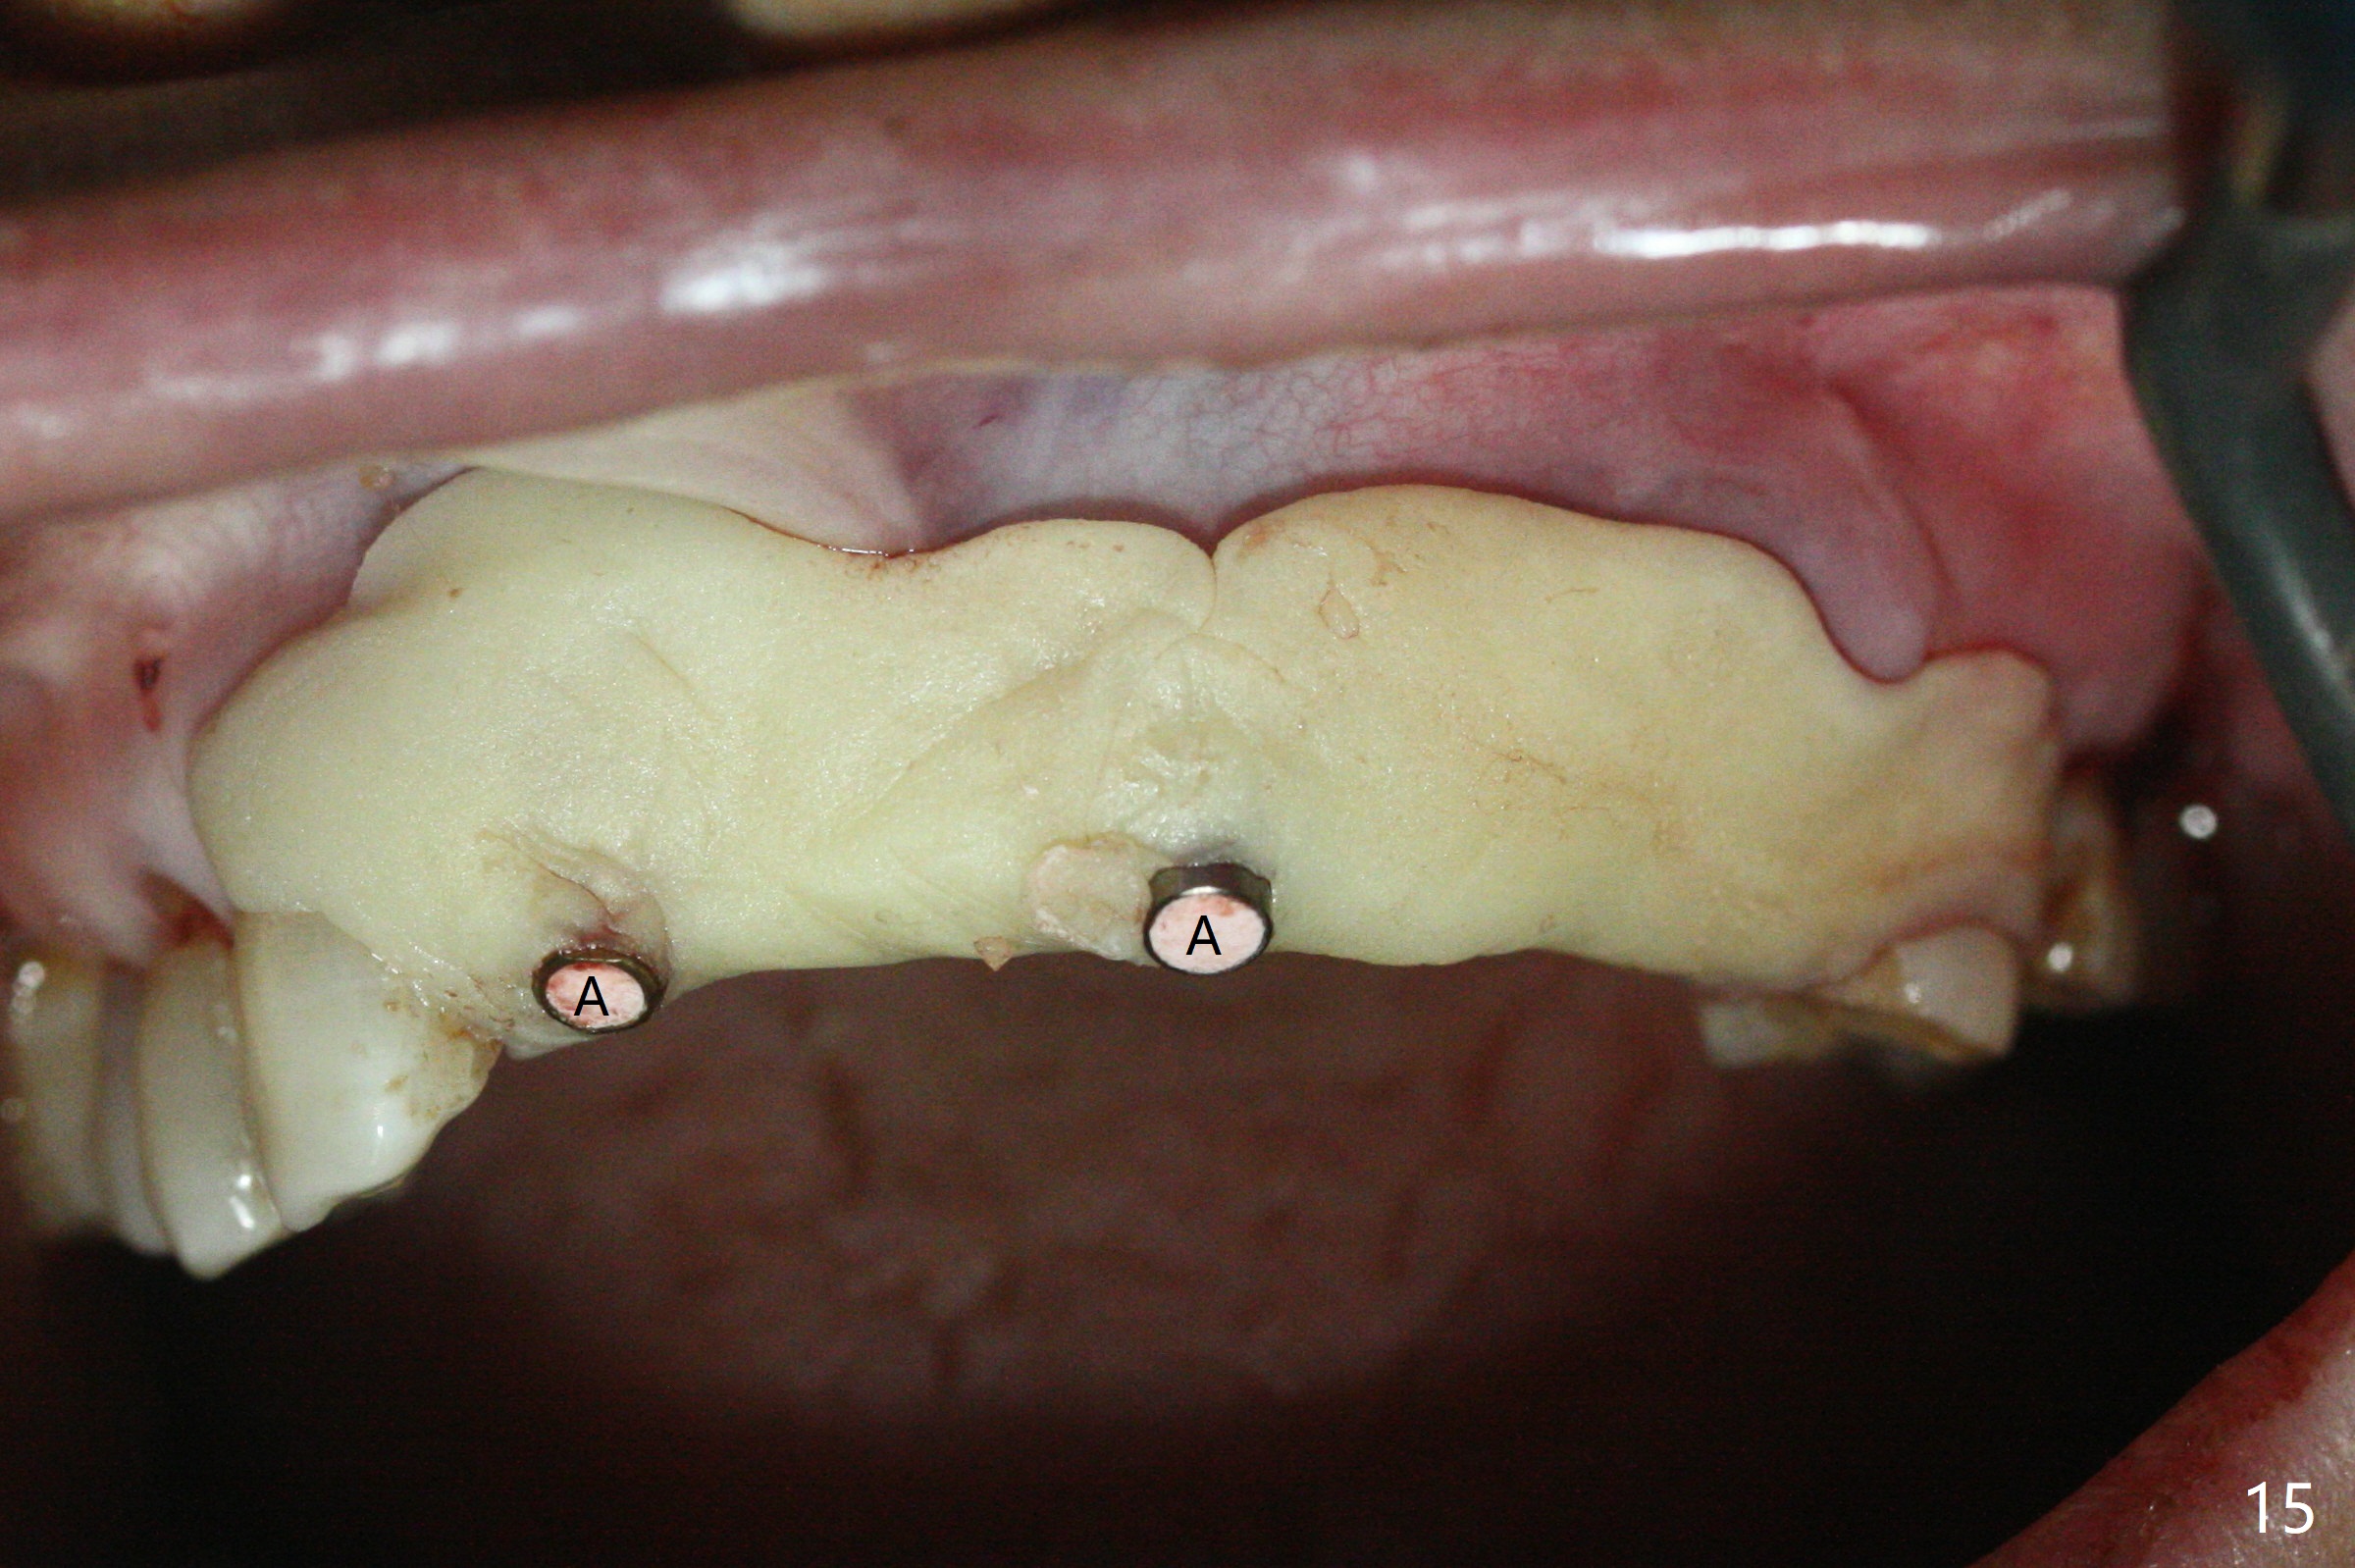

今天下午进入治疗室,粘性骨粉已制备:上清液来自红管(含促凝剂),离心3分钟(图一);再离心10分钟上清液就转变PRF,压制后,使用前剪成三块(图二:黑线),其中两块punch一个洞(图二:圆圈),插入7,9号牙基台固定;大块覆盖11/12号牙牙槽窝(图十四)。7,9,11,12号牙必须拔除(图三),然后在7,9,12种植。由于缺失左下磨牙,前牙垂直距离减少(图四)。完成9号牙位钻洞后,利用fixture mount(图五:M)植入植体,并留在原位固定导板(图六),然后7号牙种植,也留下fixture mount(图六:7,9),最后完成12号牙植入,但是后者扭力低,放置愈合螺帽(图九),而7,9号牙位放置修复基台(图七,八(使用5.5毫米profile drill后),好像基台没有完全就位。7号牙位更换基台似乎没帮助(图十),9号牙位再次放置同一个基台临床上仿佛有改变(比较图八与十二)。放置粘性骨粉后(图十一至十三),牙槽窝口覆盖PRF膜(图十四:P(A:基台)),最后使用树脂敷料固定骨粉和膜(图十五,六),基台帮助敷料固位,没有咬合干扰(图十七:*)。树脂敷料部分解决美观问题,一个月后撤除,如果植体仍有稳定性,可能制作7-10临时牙桥,可能部分维持或者恢复牙龈外形。术后一周病人主诉后面植牙和鼻底疼痛,11号牙根尖牙龈充血(图十八),轻度触痛,可能与术中尚未完全清创有关(图十九(术前CT 3D图像))。再服用Amoxicillin一周,症状好转,鼻底轻度触痛(图二十)。术后1.5月没有任何不适,撤除树脂敷料,7号牙基台(袖)显得太长,换一个短的(4.5x4(5)(图十,十一)->4x4(3)毫米)毫米),植骨好像愈合正常(图二十一:*)。7号牙换了短的基台,9号牙基台高度调整后,与对合牙有足够空间做临时牙桥,最好8,10号牙位牙龈应该凹陷(图二十二:*),有pontic外形。另外9号牙基台颊侧牙龈边缘有所修整,临时牙桥准备。先做7-10临时牙桥,理想临时牙桥pontic处树脂应该多些(图二十三:白线)压迫牙龈形成凹陷。11,12号牙牙槽窝在树脂(Bosworth)敷料下也正常愈合(图二十四)。